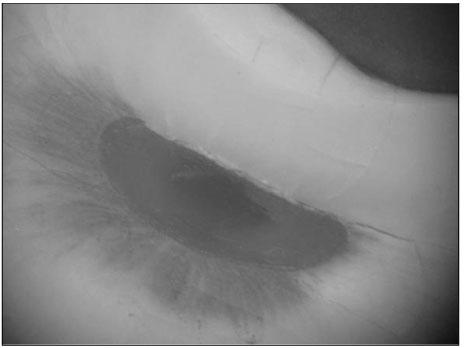

Figure 1

Photograph of the physiologic foramen of distal root (×60)

Figure 1 Photograph of the physiologic foramen of distal root (×60)